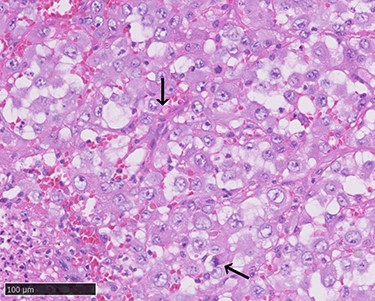

A 70-year-old Japanese woman was referred to our department. Her medical history indicated surgery, radiation therapy and intravascular treatment for AVM in her right upper limb since she was 17 years old (Fig. 1). One month before initial presentation, she noticed frequent haemorrhagic masses in her oral cavity. She complained of general malaise and loss of appetite. The masses bled readily upon scraping the hard palate (Fig. 2A). Similar masses were found on her left lower gingiva (Fig. 2B). Routine blood tests revealed normocytic normochromic anaemia of 4.6 g/dl, while no platelet or coagulation abnormalities were found. Open incisional biopsy under general anaesthesia was performed after conservative management, including blood transfusion, nutrition and oral care. The masses had grown rapidly and covered the hard palate and had spread to the upper gingiva, maxillary bone and maxillary sinus (Fig. 2C and D). The specimen consisted of bloody, dark-red and partially sponge-like lesions. Histologically, necrosis and haemorrhage were evident. In areas where viable cells were present, atypical, vascular endothelial cells with pleomorphic nuclei formed a solid lesion or a network to form a narrow lumen filled with blood cells (Fig. 3). Immunohistochemical staining was positive for CD31, CK (AE1 + 3), ERG, D2–40 and CK (CAM 5.2) and negative for CD34, FactorVIII, αSMA, MyoD1, Desmin, Myogenin, S100, HMB45, MelanA, CK (5/6), p63, p40 and EMA. MIB-1 staining showed a proliferation index as high as 50%. These pathohistological findings revealed the tumour as AS (FNCLCC Histological Grade 3).

Atypical proliferation of dedifferentiated cells with pleomorphic nuclei and atypical mitotic figures (arrows, haematoxylin–eosin stain, ×400).